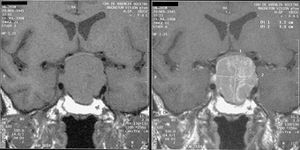

التشخيص